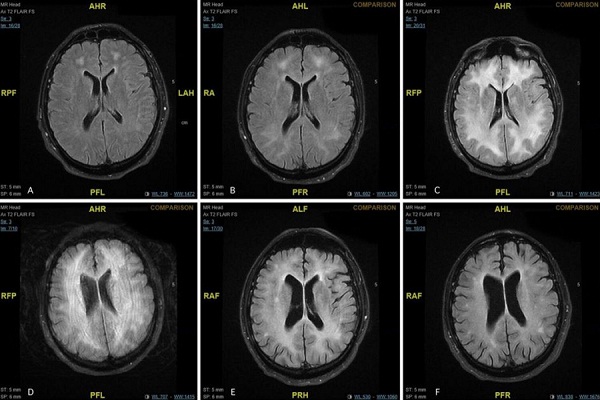

وأرسل فريق الدكتورة ييلنيا المريض لإجراء فحوصات الرنين المغناطيسي على دماغه، وكشفوا عن أضرار للمادة البيضاء في الدماغ، وقام الأطباء بتشخيصه بالحالة النادرة الناجمة عن اعتلال بيضاء الدماغ السامة (ويسمى أيضا مرضة المادة البيضاء) الناجم عن الكوكايين، والذي يكون في أغلب الحالات المماثلة قاتلا.

وبعد عام من الانقطاع عن تعاطي الكوكايين، عاد المريض للمعاينة، حيث وجد الأطباء عند فحص دماغه أنه ما تزال هناك "تغييرات دائمة في المادة البيضاء"، بينما كانت الاختبارات العصبية طبيعية.